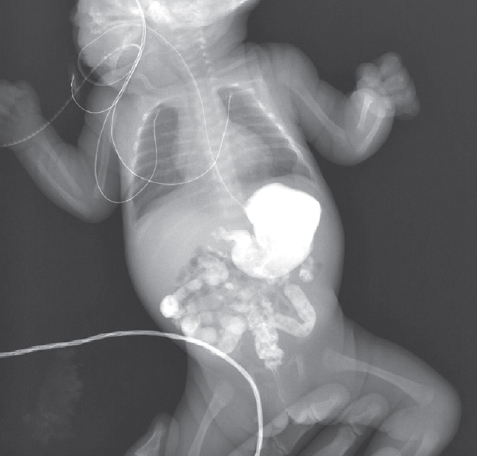

Из таблиц 1 и 2 следует, что наиболее часто встречающимися рентгенологическими признаками являлись левосторонне расположенная толстая кишка (30 %) и высокое стояние слепой кишки (39 %) (рис. 1).

Рис. 1. Левостороннее расположение толстой кишки (слева), высокое расположение слепой кишки (справа) у новорожденных, ирригография

Fig. 1. Left-sided location of the colon (left), high location of the cecum (right) in neonates, irrigography

В восьми случаях (18 %) левостороннее расположение толстой кишки сочеталось с атипичным расположением слепой кишки (высокое стояние или высокое и срединное положение) (рис. 2).

Рис. 2. Высокое и срединное положение слепой кишки у новорожденного, ирригография

Fig. 2. High and medial position of the cecum in a newborn, irrigography